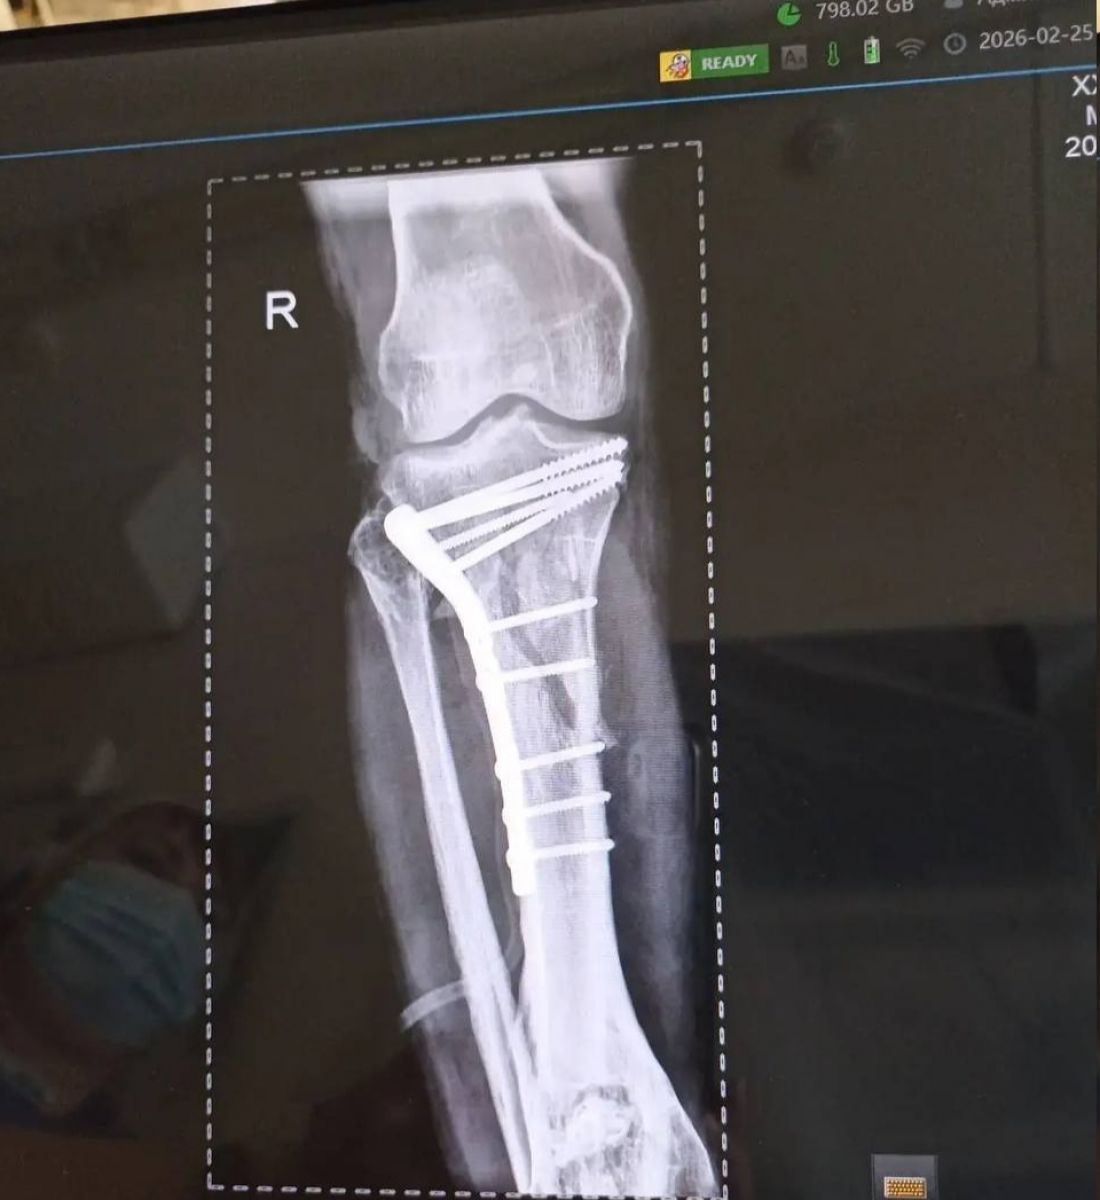

Врачи городской больницы № 4 «Липецк-Мед» провели сложнейшую 3-часовую операцию, чтобы спасти мужчину, который попал в страшное ДТП 25 февраля. При поступлении медики диагностировали у него внутрисуставные переломы верхних отделов обеих голеней – они были раздроблены.

Оперировала мужчину бригада во главе с завотделением травматологии Дмитрием Соколовым и травматологом Евгением Крюченковым. Хирурги приняли решение оперировать сразу обе ноги. Почти три часа врачи по кусочкам собирали разрушенные кости голеней.

Сейчас самое опасное позади, пациента уже перевели из реанимации в профильное отделение. Его состояние стабилизировалось. Теперь ему предстоят повторные операции, чтобы убрать скрепляющие конструкции после сращения костей, а затем долгий процесс восстановления и реабилитации.